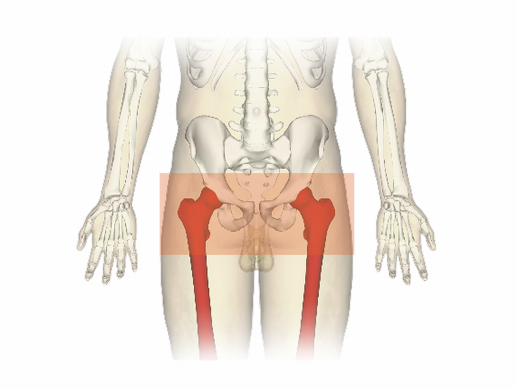

Pelvic Fractures are a high energy injury, however in the elderly or frail less force may be required. It can cause disruption of blood vessels leading to major haemorrhage with a risk of death. Identifying these patients and treating the injury can be life saving. By applying a pelvic binder if you have suspicion you may be able to stabilise your patient.

Pelvic binder should be centred over the greater trochanters – it is a common mistake to site them too high.

Position for application of (Tpod) Pelvic Binder